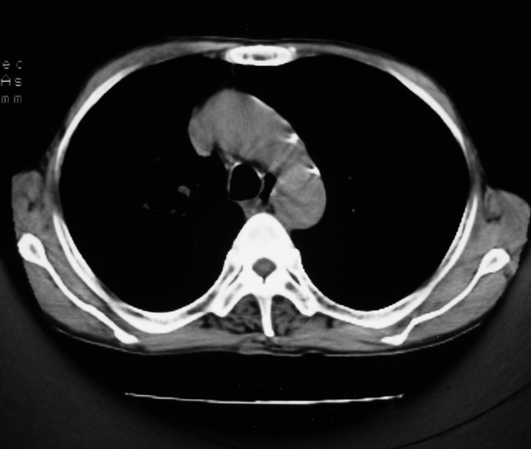

以下是引用同在2007-1-27 14:13:00的发言:[br]支持右侧中央型肺癌伴阻塞性病变.

以下是引用zjzjr在2007-1-27 16:56:00的发言:[br]支持右肺中心型肺癌伴阻塞性肺炎.